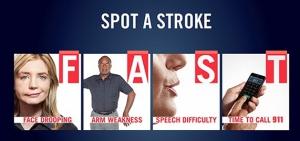

3 signes qui engagent à agir vite (FAST) : une déformation du visage, une faiblesse dans les bras et une difficulté à s'exprimer doivent inciter à se rendre très rapidement aux Urgences.